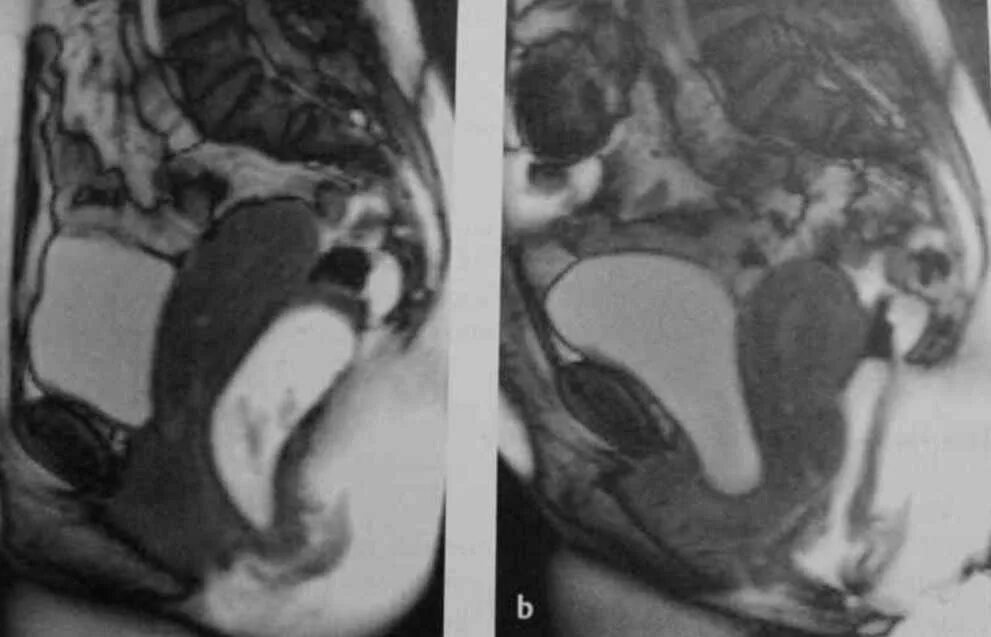

Опущение органов малого таза у женщин операция